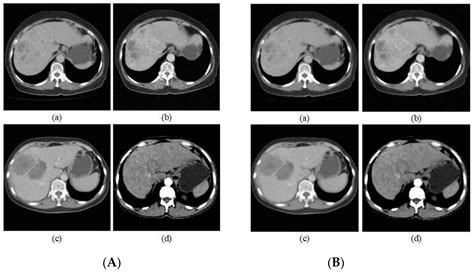

Interpreting Liver Anomalies on CT

Lesions detected during a scan are categorized by their density and how they "enhance" (light up) after the contrast dye is injected. A simple cyst, for instance, will remain dark and show no enhancement, while a hemangioma typically shows peripheral, nodular enhancement that slowly fills toward the center. Malignant tumors often exhibit "wash-out," where the contrast enters the lesion quickly but leaves it faster than the surrounding healthy liver tissue.